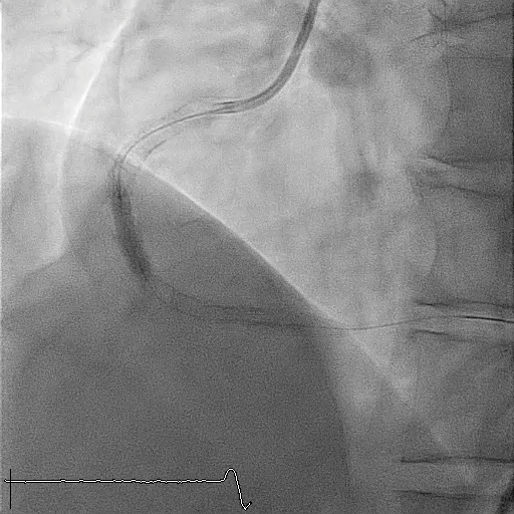

Subsequent coronary angiography identified a pseudoaneurysm in the right coronary artery (RCA), without any evidence of extravasation.

In this coronary catheterization procedure, a guidewire was used to cross the lesion and advanced to the posterolateral branch (PL). An intravascular ultrasound (IVUS) examination was conducted, revealing a pseudoaneurysm in the mid-right coronary artery (m-RCA). To cover the pseudoaneurysm, a 3.5 x 16 mm cover stent was deployed in the m-RCA at a pressure of 16-18 atmospheres for 15-20 seconds, repeated twice. Subsequently, the cover stent was further post-dilated with a 3.75 x 15 mm non-compliance balloon at 18-20 atmospheres for 10 seconds, also performed twice. Optical coherence tomography (OCT) was then performed, showing a post-dilation stent MSA of 7.40 mm² with good apposition and expansion. The cover stent was additionally dilated with a 4.0 x 30 mm drug-eluting balloon (DEB) at 6 atmospheres for 60 seconds. The final angiography demonstrated TIMI grade 3 flow without any extravasation.

Case Summary

Post-intervention angiography demonstrated improved blood flow in the affected artery. The RCA pseudoaneurysm was effectively sealed, and subsequent imaging confirmed appropriate stent placement. The use of IVUS and OCT allowed for optimal sizing and placement, leading to a successful outcome.